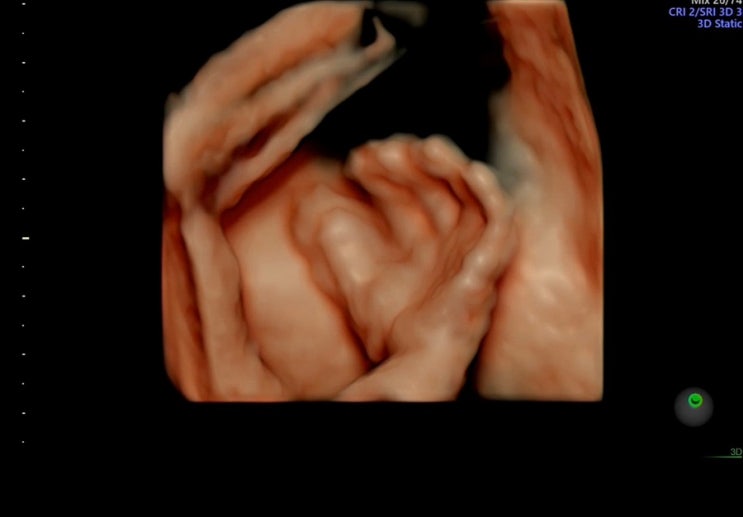

9월14일 33주 5일의 꾸용이 기록 -! 머리둘레 8.58cm 복부 29.10cm 허벅지길이 6.38cm 무게는 2189g 드디어...